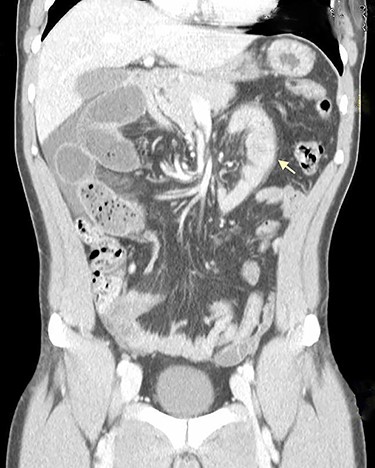

On physical examination, he was eupneic, hemodynamically stable and apyretic. His abdomen was soft, not distended, painless, with normal bowel sounds. Rectal examination showed an empty ampulla. Blood analysis revealed mild leukocytosis and little increase in C-reactive protein. Plain radiograph of the abdomen revealed dilated small bowel loops with air/fluid levels. Abdominal ultrasound revealed swollen intestinal loops on the right flank and interloop fluid. For further clarification, abdominal and pelvic computed tomography (CT) scan showed small bowel distension, air/fluid levels and free fluid (Fig. 1); signs of intestinal malrotation, with alteration of the normal topography of the duodenal arch (Fig. 2) and retrocecal position of terminal ileum (Fig. 3).

Sagittal CT scan shows small bowel distension with air/fluid levels (arrows).